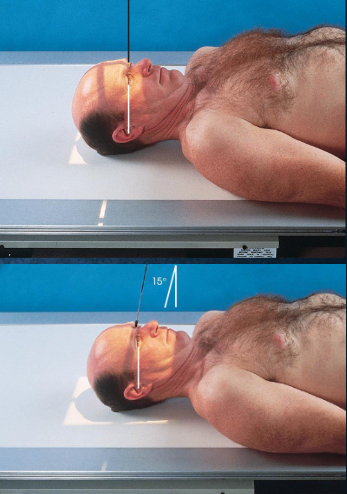

PA/PA axial (Caldwell) skull

patient position:

seated upright or prone

MSP centered to midline

forehead and nose resting on Bucky

part position:

MSP and OML perpendicular to IR

respiration suspended

CR:

PA: perpendicular to IR, exiting nasion

PA axial: 15 degrees caudad, exiting nasion

collimation:

1 inch beyond skin line of the skull

PA skull image criteria

evidence of proper collimation

entire cranial perimeter showing three tables of squamous bone

no rotation:

equal distance from lateral borders of skull to lateral border of orbits

symmetric petrous ridges

petrous ridges fill orbits

penetration of frontal bone without excessive density of lateral borders of skull

PA axial (Caldwell) skull image criteria

petrous ridges demonstrated in lower third of orbits

AP/AP axial (Reverse Caldwell) skull

a similar but magnified image when patient cannot be positioned for PA or PA axial

patient and position part:

supine

MSP centered to midline

MSP and OML perpendicular to IR

respiration suspended

CR:

AP: perpendicular, enters nasion

AP axial: 15 degrees cephalad, enters nasion

collimation:

1 inch beyond the skin line of the skull

AP/AP axial (Reverse Caldwell) skull image criteria

shows the same as PA and PA axial projections

evidence of proper collimation

entire cranial perimeter showing three tables of squamous bone

no rotation:

equal distance from lateral borders of skull to lateral border of orbits

symmetric petrous ridges

anatomy is more magnified